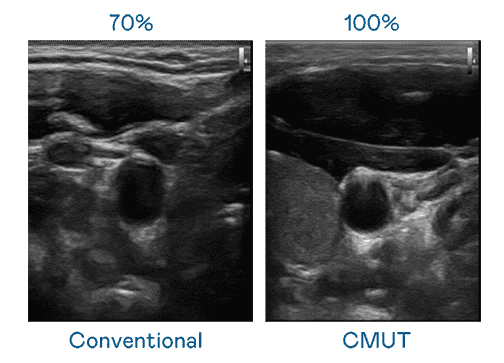

CMUT 技术是一种用电容式微机电元件来产生超音波讯号的技术。。。。与传统 PZT 压电式技术相比,,,,CMUT 频宽增加 30%,,,更宽频的超音波讯号让影像解析度大幅提升,,,,是实现高影像品质医疗超音波扫描、、促进精准医疗发展的关键技术。。。

超音波影像的解析度高低,,,,首先取决于探头能发出的讯号频宽。。。优游UB8 CMUT 可提供高清晰的超音波讯号,,,提供高频宽、、、、高灵敏度、、、、影像纹理细节更高的超音波影像,,,,协助医护人员缩短影像判读时间及利用精准的医疗影像进行诊断。。。